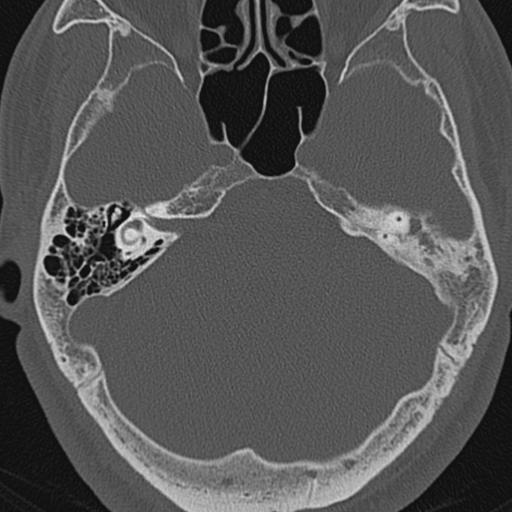

以下是引用zxl51642在2009-8-25 13:37:00的发言:[br]1、左侧慢性硬化型中耳乳突炎(中耳鼓室腔及听小骨受累),并胆脂瘤形成;2、左侧外耳道软组织密度影填塞,考虑炎性肉芽肿,建议结合临床;3、右侧颈静脉窝较左侧明显扩大,不排除颈静脉球瘤,建议mr进一步检查。

以下是引用随光逐影在2009-8-25 19:05:00的发言:[br]1)左侧慢性中耳乳突炎(肉芽肿或胆脂瘤形成),左侧外耳道炎性肉芽肿。2)右侧颈静脉球高位。